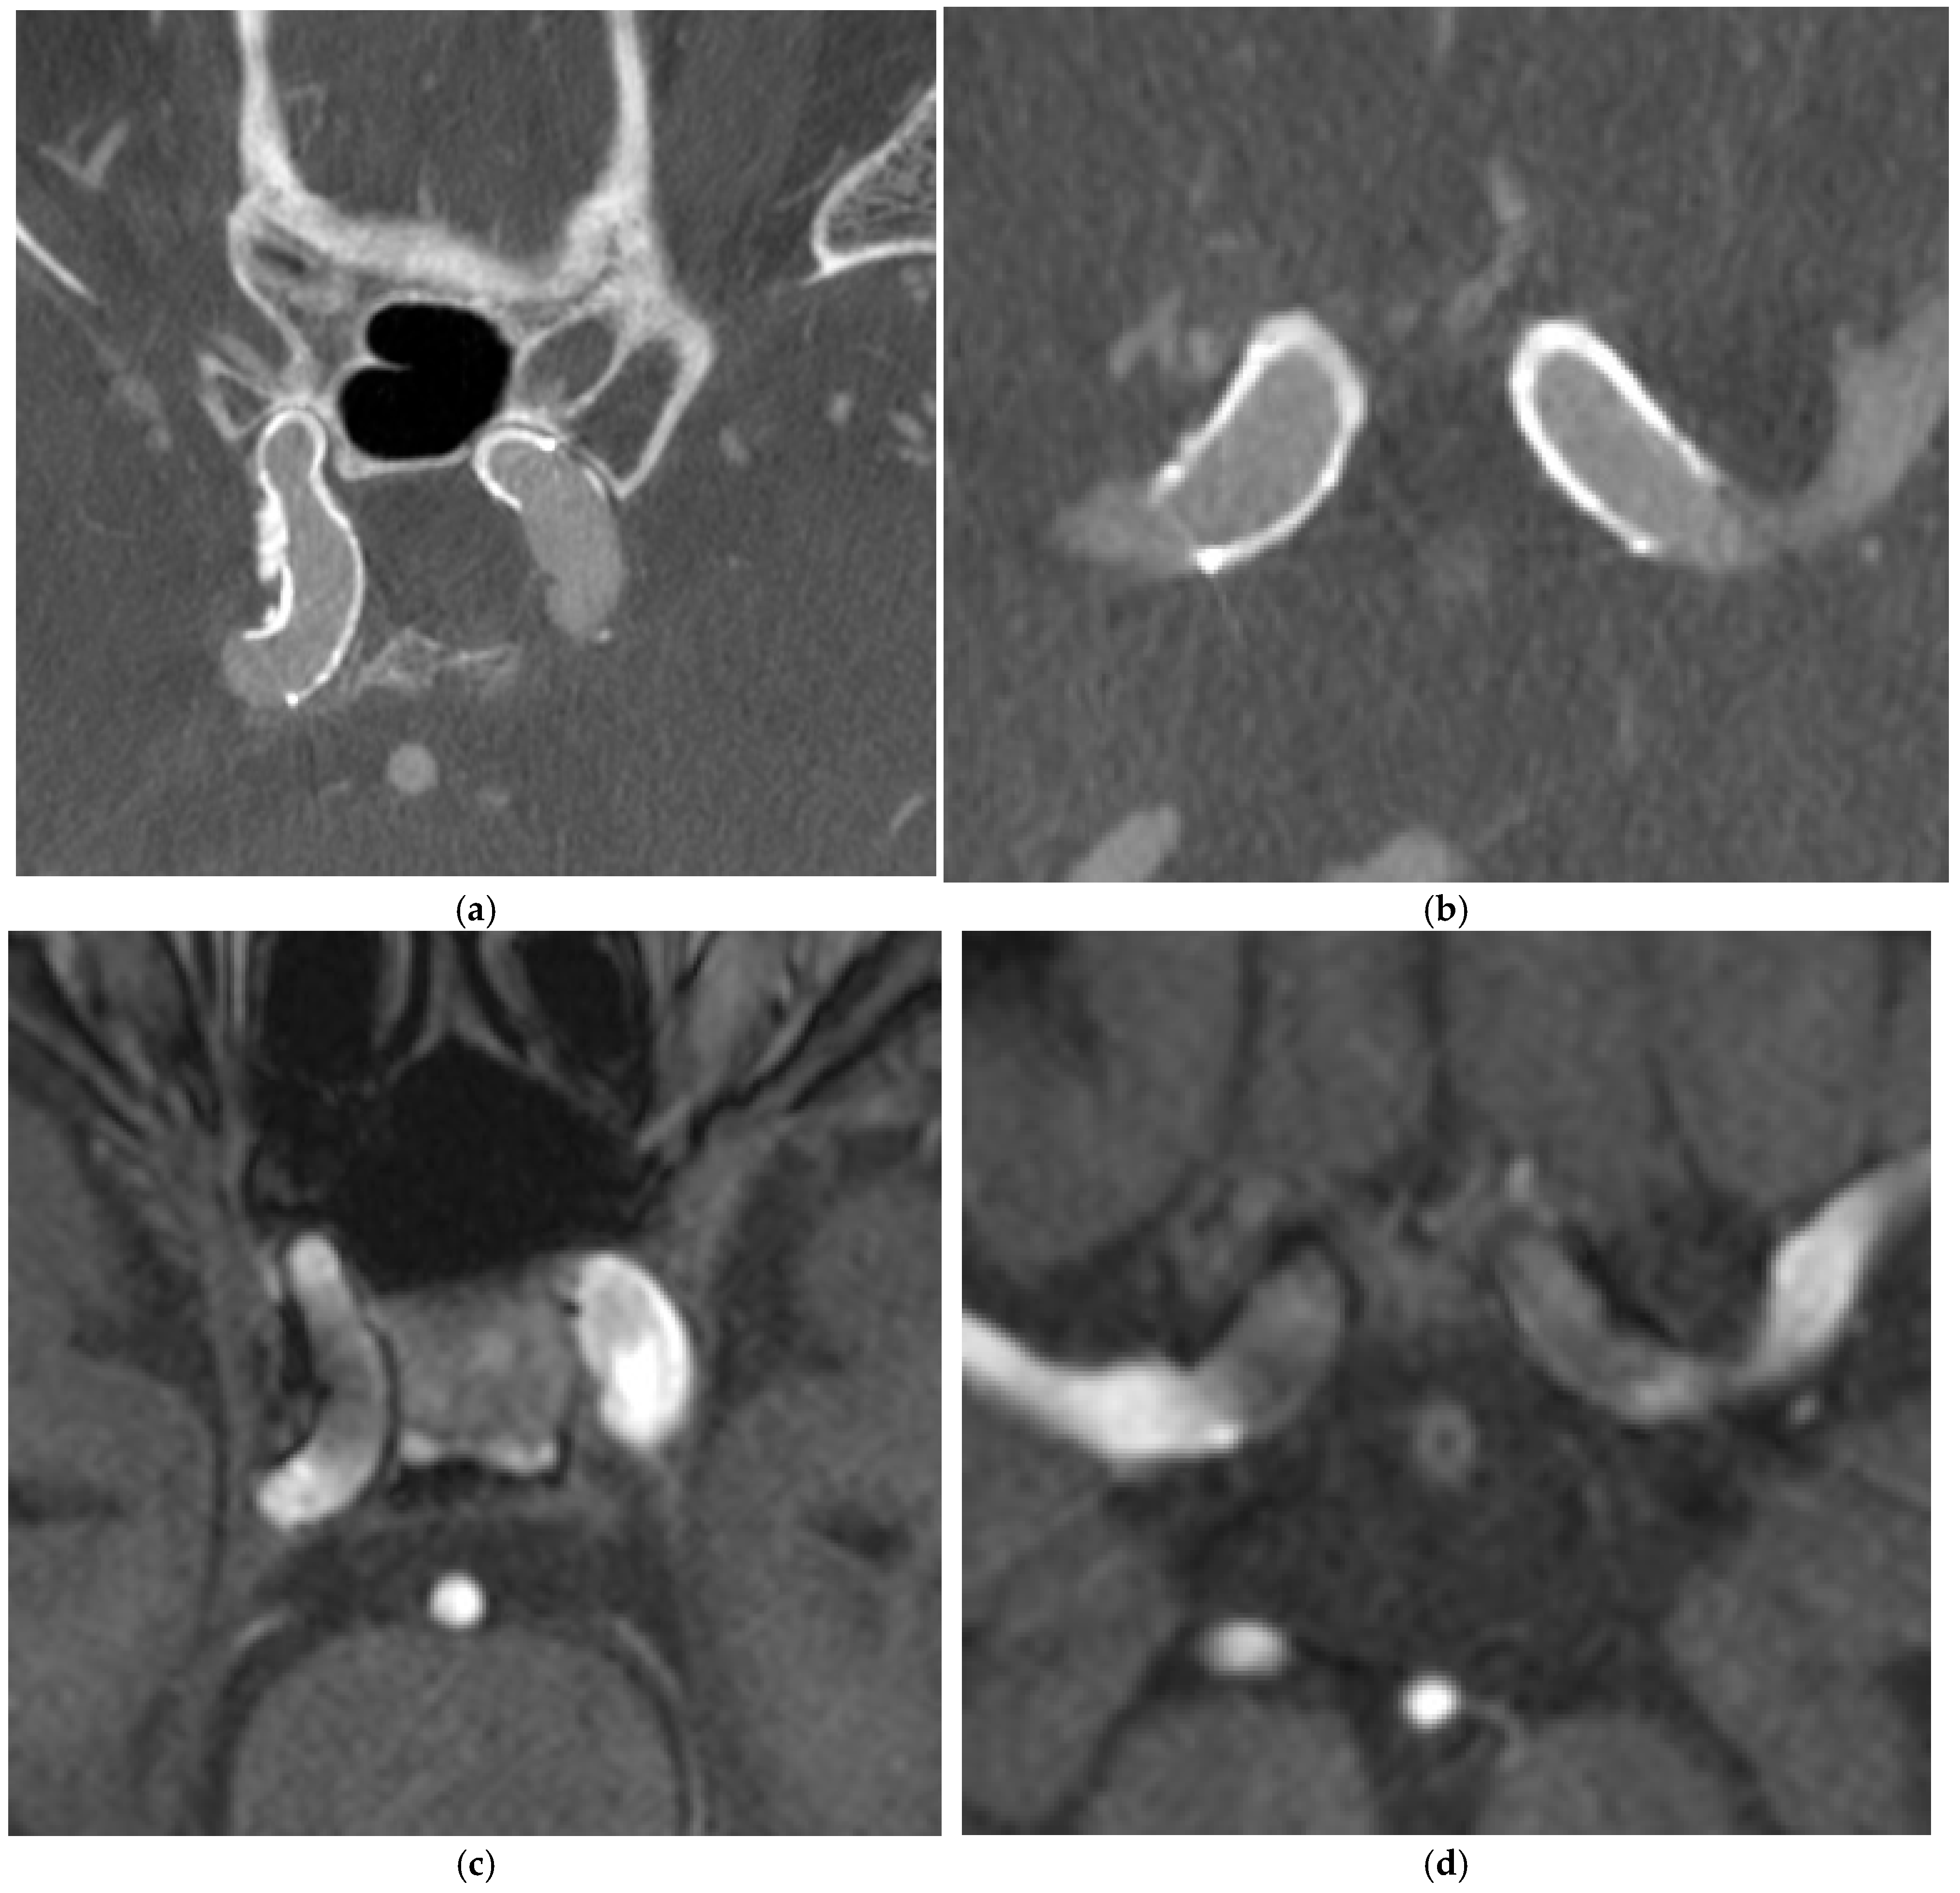

4.1. Case 1

4.2. Case 2

4.3. Case 3